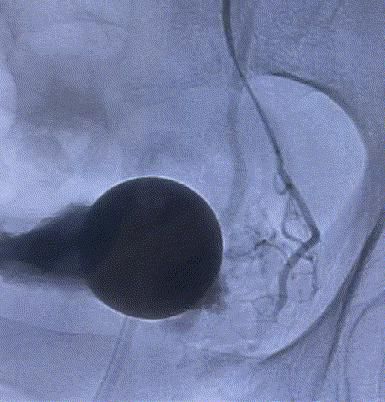

我院這項“很牛”的技術——介入下前列腺動脈超選擇栓塞術,能讓前列腺增生“由大變小”。該技術無須切開任何組織,僅通過股動脈穿刺置入微導管,經動脈的自然腔道,送達前列腺動脈,将PVA材料置于雙側前列腺動脈即可完成手術。其原理是阻斷前列腺營養供給,使其逐漸萎縮變小,從而解除對膀胱、尿道的壓迫,達到治療的目的。

随後,李旭丹主任攜手胡志華主任爲患者實施介入治療,采用改良Seldinger法穿刺股動脈,在DSA引導下經動脈自然腔道,将微導管分别送達雙側髂内動脈進行造影,觀察雙側前列腺動脈分布情況,将微導管超選擇至雙側前列腺動脈,準确置入PVA栓塞材料,成功阻斷前列腺的營養供給,順利完成了治療。